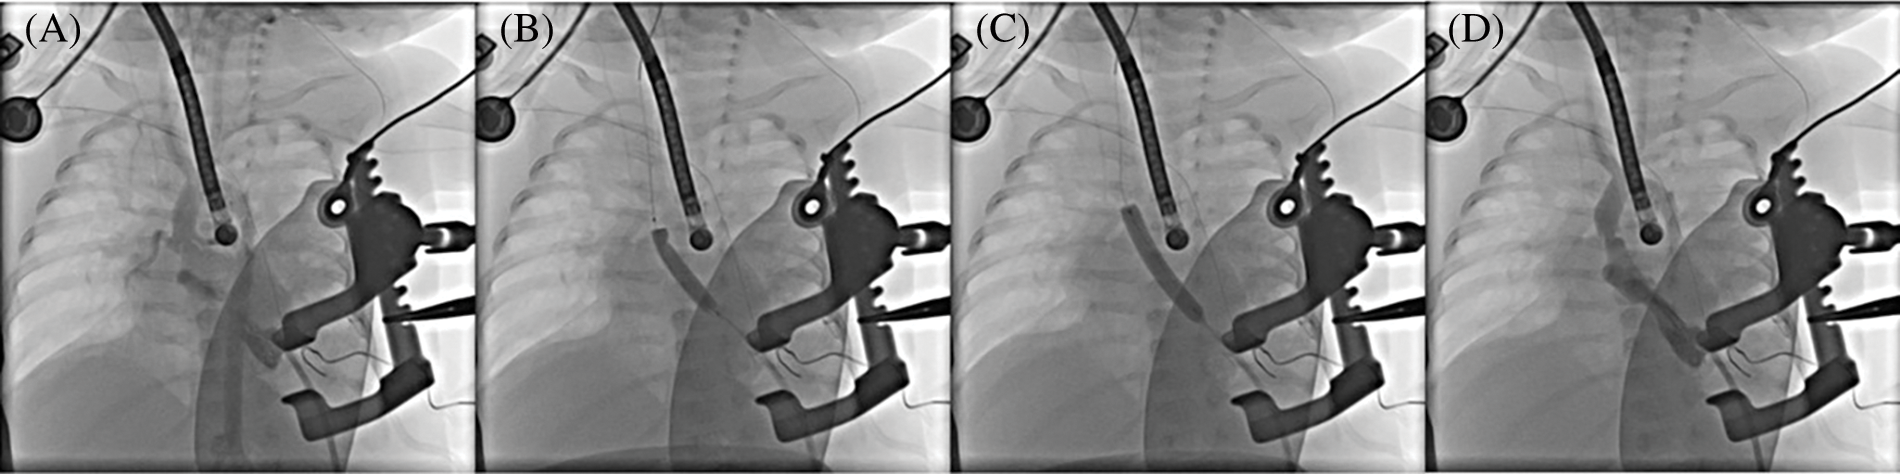

Figure 2: Aortic valvular balloon valvuloplasty. (A) Aortic valvular stenosis and dome-like changes in the valve orifice before balloon valvuloplasty; (B) 5 mm balloon valvuloplasty; (C) 6 mm balloon valvuloplasty; (D) Significant improvement in aortic valve stenosis after balloon valvuloplasty